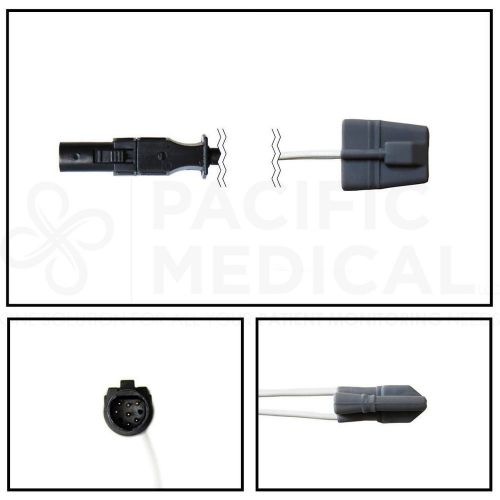

GE Datex-Ohmeda Hypertronics Adult Soft Shell SpO2 Sensor 10' Cable Yr Warranty

GE Datex-Ohmeda Marquette Adult Soft Shell SpO2 Sensor 10' Cable New Yr Warranty

GE Datex-Ohmeda Hypertonics Pediatric Soft Shell SpO2 Sensor 10' Cable Warranty

GE Marquette Adult Soft Shell SpO2 Sensor 10' Cable New Yr Warranty